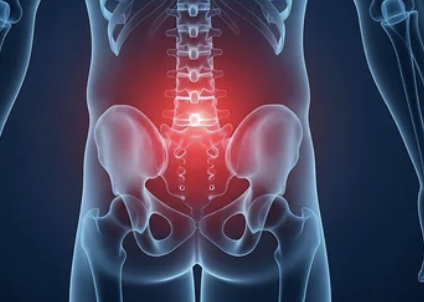

6️⃣ 목·두통·전신 피로

- 골반 틀어짐 → 척추 전체 불균형 → 목·어깨 긴장 증가

- 두통, 만성 피로, 집중력 저하로 이어짐

👉 단순 하체 문제를 넘어 전신에 영향을 줍니다.